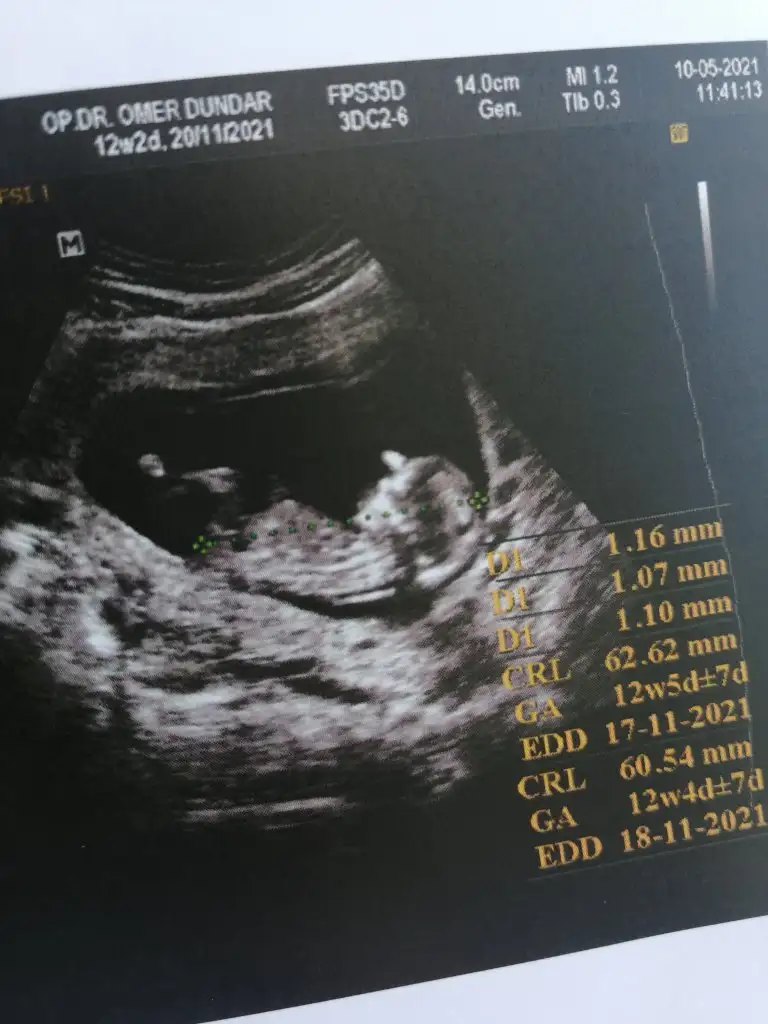

Cinsiyet tahmini alayım kızlar

Eki Görüntüle 2846054

Maşallah allah sağlıkla kucağınıza almayı nasip etsinBide 4 boyutlusu var

ErkeeeekkkkkBu da resmimiz tahmin alabilirim

Erkek sankiBu da resmimiz tahmin alabilirim

Kız diyorumCinsiyet tahmini alayım kızlar

Erkek gibi %60 oran vereyim net bişey daha söylemeyim dedi bakalımErkek sanki

Kız diyorum

Kızlar bakalım tutacak mı tutarsa etıketleyın benı

Saglıkla dogsunlar inşallah canımErkek gibi %60 oran vereyim net bişey daha söylemeyim dedi bakalım